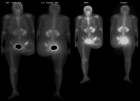

53 year old female with pelvic pain and fevers

History of left hip disarticulation due to a 2005 motor vehicle accident